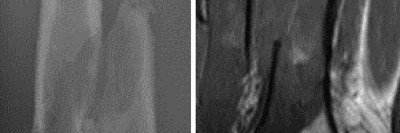

Warum nimmt die Oberschenkelschwellung beim Dialysepatienten immer mehr zu?

Bei einem 54-jährigen Mann nimmt seit einem halben Jahr die schmerzhafte Schwellung der rechten Hüfte bei bekannter Peritonealdialyse zu. Es besteht eine chronische Niereninsuffizienz. Vier Jahre zuvor war eine Parathyroidektomie bei tertiärem Hyperparathyreoidismus durchgeführt worden. Was zeigen Röntgen- und MRT-Bilder?

Chondroblastom in der MRT/© Camp L et al. / all rights reserved Springer Medizin Verlag GmbH, Patellafraktur/© K. Fehske · R. Hoffmann / all rights reserved Springer Medizin Verlag GmbH, Röntgenaufnahme eines nicht ossifizierenden Fibroms /© Weber M et al. / all rights reserved Springer Medizin Verlag GmbH, Cholesterolgranulom im MRT/© Frederik F/ all rights reserved Springer Medizin Verlag GmbH, pathologische distale Femurfraktur/© Omar M et al. / all rights reserved Springer Medizin Verlag GmbH, Frau unkenntlich fasst sich ans Knie/© Pornpak Khunatorn / Getty Images / iStock (Symbolbild mit Fotomodell), Echondrom/© Springer Medizin, Ausprägungen einer antiresorptivaassoziierten Kiefernekrose (AR-ONJ)/© Ristow, O. et al. / all rights reserved Springer Medizin Verlag GmbH, Stereotaktische Strahlentherapie (SBRT) einer solitären ossären Metastase in dem Brustwirbelkörper/© Springer Medizin Verlag GmbH, Arzt oder Pfleger schaut auf eine im MRT Eingang liegende Person/© [M] oksanazahray / stock.adobe.com (Symbolbild mit Fotomodell), Wirbelsäulenmetastase/© stockdevil / stock.adobe.com, Bluttransfusion/© Tobilander / Fotolia, Ärztin und kleines Mädchen mit Kopftuch/© FatCamera / Getty Images / iStock (Symbolbild mit Fotomodellen), Inhalt eines Fläschchens wird aufgezogen/© MarianVejcik / Getty Images / iStock, aneurysmatische Knochenzyste im Bereich des rechten distalen Femurs/© Springer Nature / all rights reserved Springer Medizin Verlag GmbH, Ewing-Sarkom/© Botos B. Z. et al. / all rights reserved Springer Medizin Verlag GmbH, Tumorkalzinose in der Hüfte/© Sukun A & Weber M.-A. , Computertomografie-gesteuerte periradikuläre Therapie auf Höhe von Lendenwirbelkörper 5/Sakralwirbelkörper 1 rechts/© Institut für Diagnostische und Interventionelle Radiologie des Klinikums St. Marien Amberg, Körperstereotaxie einer Lebermetastase im Segment VIII am MR-LINAC/© Ehret, F. et al. / all rights reserved Springer Medizin Verlag GmbH, Search Icon, Arthropedia, Ärzteteam führt Hüftoperation durch/© ATRPhoto / stock.adobe.com (Symbolbild mit Fotomodell), Gebrochener Fuß im Gips/© Aleksandr Kirillov / stock.adobe.com (Symbolbild mit Fotomodell)